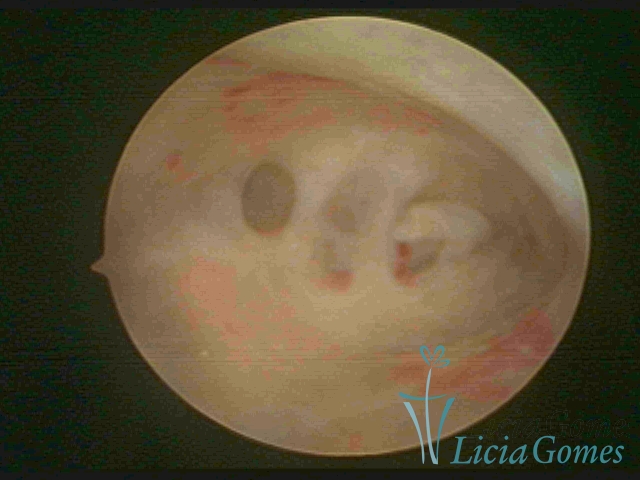

• SINÉQUIA TIPO FIBROMUSCULAR